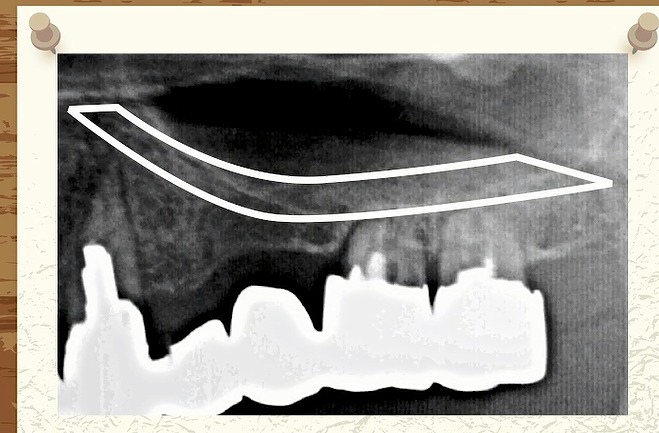

レントゲン写真は硬いものが白くうつります。

↑

ここに白い線がはっきりくっきりと

うつっています。

ここには

硬い骨

太い骨

があるのです。

ではこの硬い骨、太い骨は

どういう役目があるのか?

この硬い骨と太い骨は

口の部屋と鼻の部屋が混ざらないように

仕切っている壁なんですね。

口側には

歯の頭と歯の根っこと

その根っこを支える骨が

あります。

硬い骨と根っこの間には隙間(骨)があります。

これは

鼻の部屋を分けている

硬い骨です。

そして反対側です。

左側のはっきりくっきりした線に比べると

右側は

途中までははっきりした線がありますが

しかし赤丸の一番大きい歯のところは

はっきりと線が見えません。

人間の体は

だいたい左右対象的ですから

本来の鼻のラインはどこか?

ちょっと右と左でうつり方が違いますね。

本来ならば硬い骨よりも

口側に

歯の根っこや骨が入っていないといけません。